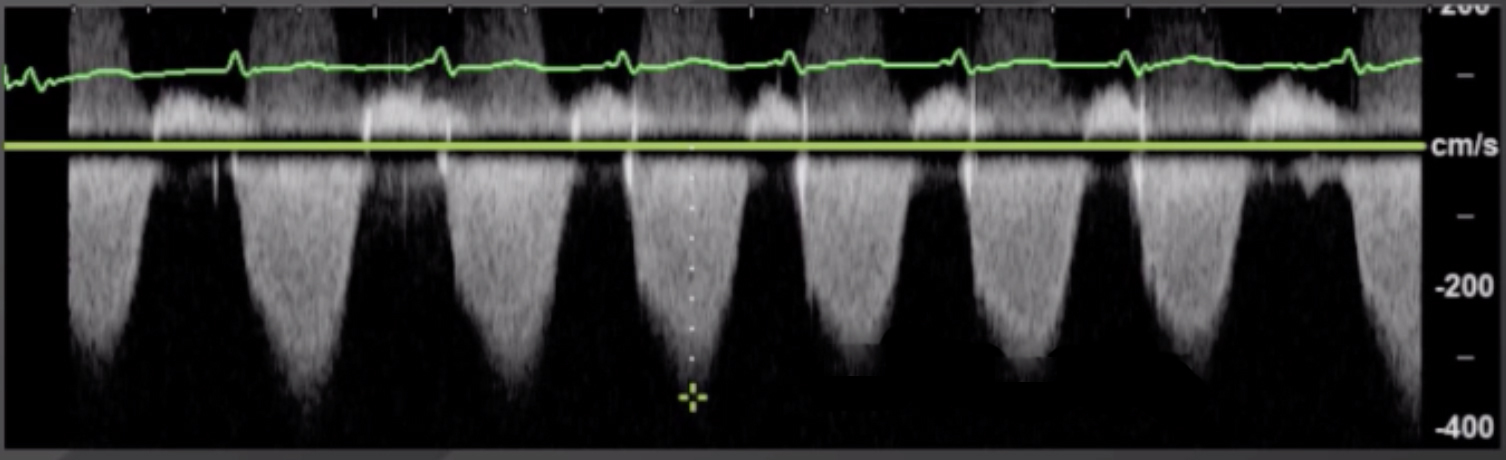

Cardiac 2 RVSP Calculation Image